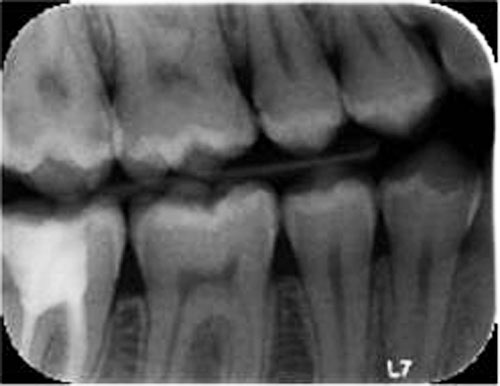

Inferring 3D from 2D: Even when it is clear that understanding dental health in three dimensions is the goal of any dental diagnostic task, bitewing radiograph is still the standard of care to diagnose dental pathologies because of its lowered radiation exposure, wide availability, speed and low cost. Thanks to advances in shape analysis, AI and more widely available 3D datasets, it is possible to derive 3D information from inherently 2D imaging techniques. Our team has performed extensive work in this area, see more information here.